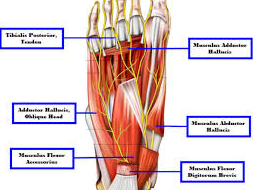

The rating schedule refers to Group X muscles as one of the groups of muscles of the forefoot and toes. Functions of the plantar and dorsal muscles include:

Signs and symptoms of injury to muscles in this group may range from severe to mild. Manifestations of injury may include varying degrees of limitation in the flexion, extension, and abduction of the toes, in general. Reduced function in flexion of the metatarsophalangeal joints and the extension of the distal phalanges are presented. In addition, limitations in the function of the following toes are presented: flexion and abduction of the little toe; and abduction, adduction, flexion and extension of the great toe.